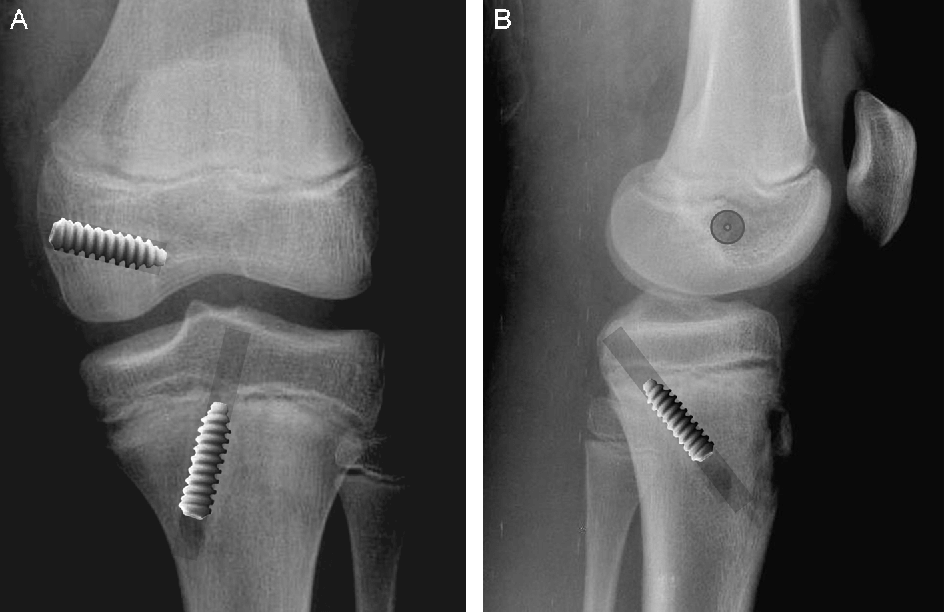

- Hobanage method: after reducing the fracture, 2 threaded brooches are inserted, under radiological control, from the proximal to the distal fragment, subsequently the fixation being super stabilized with a wire. Also, a 4.5 or 6.5mm partially threaded screw can be used depending on the dimensions of the ulnar canal.

![]() | ![]() |

- Fixation with anatomically premulated plate and screws Our medical team prefers this method of fixation due to the superior quality of the implant. The plate is made of titanium and fits perfectly on the bone surface. The assembly is stabilized with 6-8 3.5mm screws.